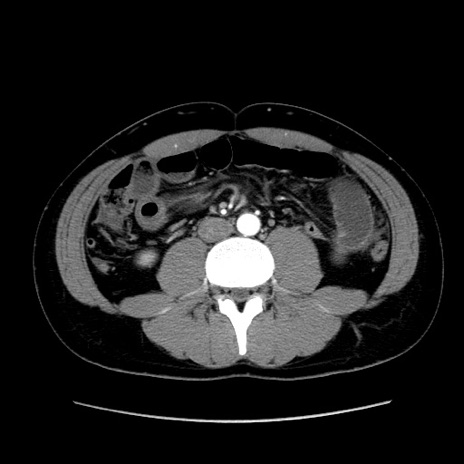

症例36(横断像)

【症例】20歳代 男性

【主訴】心窩部痛

【現病歴】今朝より上腹部痛あり。一旦軽快していたが再度出現したため救急要請。昨日夕に白身の魚を含む刺身を食べた。

【身体所見】BP 136/89mmHg、HR 74/min、BT 37.0℃、腹部:膨満、軟、心窩部に圧痛あり。反跳痛なし、筋性防御なし、腸雑音やや亢進あり。

【データ】WBC 17700、CRP 0.48